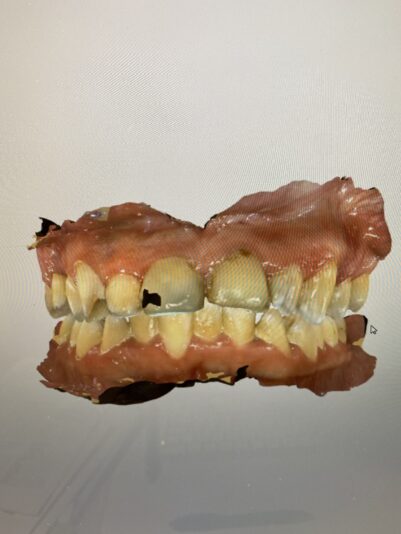

If you have time for another – how would you manage this case? 33yr old male with a chronic abscess and draining sinus tract from tooth 21 (or 9). External resorption on the middle to apical parts of the root were confirmed in CBCT. What type of bone grafting would need to be done / ie how do you repair the buccal plate? how long do you wait to graft after the initial extraction is done? Do you provide an essix as a temporary?

Here are his scans. Not sure if this bite is entirely accurate but there is no contact on the two centrals.